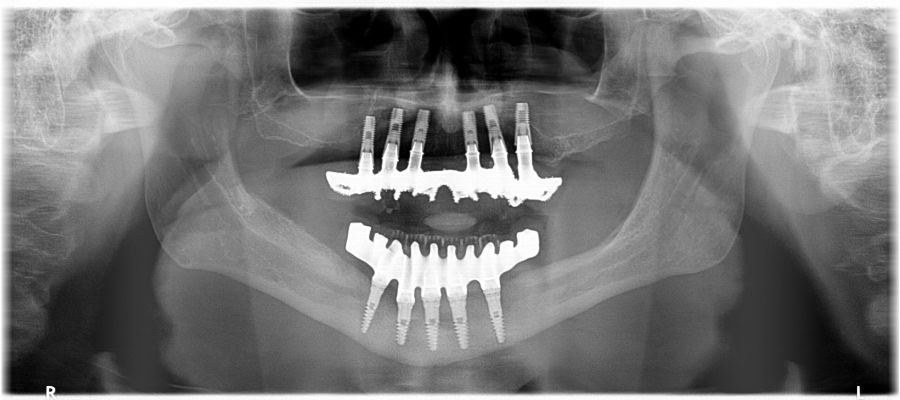

We present the clinical case of a 65-year-old patient with an implant-supported dentoalveolar rehabilitation on implants in the upper arch, placed in 2010, on which he referred pain, mobility and suppuration. After an orthopantomography, we observed a severe generalised perimplantitis in the upper arch, affecting all implants (Figure 1). It was explained to the patient that it was not possible to perform a bone regeneration of the lost tissues.

The patient has been checked every six months this year, performing X-rays and cleaning the structure, without finding any prosthetic or periodontal complications.